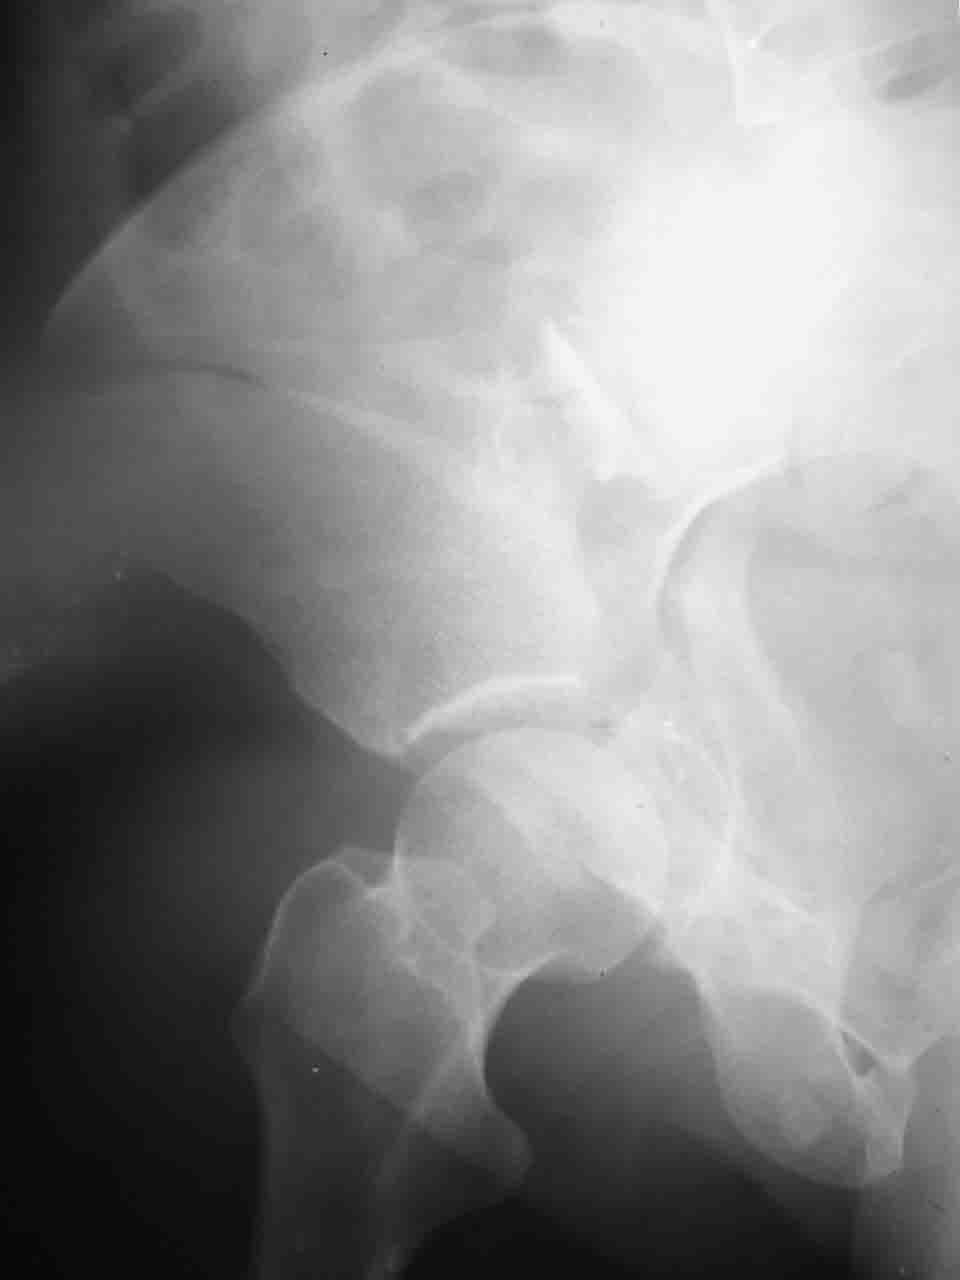

Интерес к реконструкции вертлужной впадины у меня появился довольно-таки давно, но до недавнего времени как-то не ощущалась готовность к практической реализации, а местный подход достаточно консервативен - перелом срастется,

а далее будет видно. Такую точку зрения я не разделяю, поэтому через конференции,ортофорум и свои случаи пытаюсь практически и теоретически *продвинуть* для себя тему реконструкции вертлужной впадины.

Логика подсказывает, что все-таки лучше иметь анатомически полноценную впадину, хотя ранее упоминалось состояние вторичной конгруэнтности и одно наблюдение у меня есть, когда у больного с полностью нарушенной анатомией впадины и подвывихом головки бедра кзади и кверху боли отсутствовали при относительно достаточном для стиля жизни больного объёме движений. Но это только одно наблюдение и кроме перелома впадины у этогобольного была и тяжелая ЧМТ в анамнезе. Основываясь на формулировке структуры ацетабулюм Э. Летурнеля - как перевернутой буквы Y, впадина для полноценной функции сустава должна иметь сферичность, соответствующую размеру головки бедра и если один из компонентов в дефиците, то функциональные последствия рано или поздно проявятся.

Сложностью, ассоциативностью характера перелома, я бы с радостью воспользовался мининвазивной перкутанной фиксацией винтами, но боюсь, что результат был бы ещё хуже, техникой непрямой репозиции перелома не владею, поэтому пытаясь получить анатомичную впадину приходится широко открывать, по крайней мере пока, а дальше буду пытаться уменьшать пространство...

Илеофеморальный доступ не совсем передний и сравнительно с илеоингвинальным, и Кохера-Лангенбека открывает весь наружный таз кроме самых передних отделов лонных костей, фиксацию которых я не ставил в задачу. Обширность диссекции, большая длительность операции и более высокий риск гетерооссификации - отрицательные моменты в обмен на возможность легче ориентироваться.